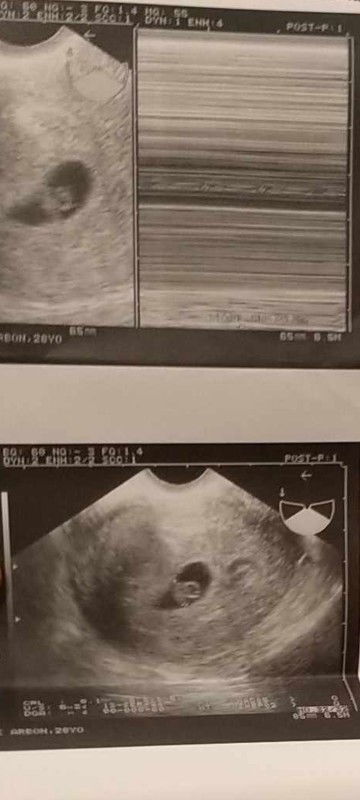

My first Trans V

Hello po mga momsh! ask ko lang po if ganyan po ba talaga pag 6weeks and 3days na? first baby ko po sya. Actually irregular po talaga ko mag mens. So for me his/she's a miracle. unexpected po talaga. akala ko normal na delayed lang ako. pero pag pt ko nag positive sya. Nag worried ako baka mahina kapit nya but sabi ni ob malakas daw, then yung heartbeat po nya is 148. yung iba kasi nababasa ko dito 5weeks na wala pa din ma detect na baby? thank you po sa sasagot. wala po talaga ko any idea eh.